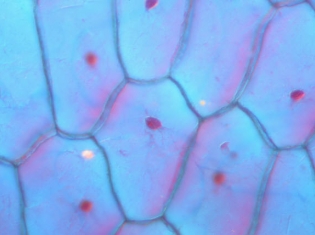

The research team found that mutations reducing the expression of glucocerebrosidase lead to excess glucocerebroside lipid in cultured neurons. By interacting with α-syn, those glucocerebroside lipids induce accumulation of the protein.

Brain tissue samples from a mouse model of Gaucher's and from patients with either Gaucher's or Parkinson's-related disorders also showed evidence connecting reduced glucocerebrosidase expression with increased α-syn deposition in neurons.

In both the cultured cells and in the animal and human samples, α-syn deposits were also associated with neurodegeneration.